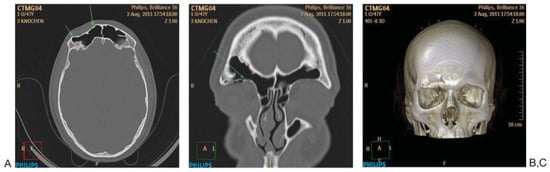

Systematic evaluation of the skull base and cranial vault in CT (Figure 4) begins with the evaluation of axial slices from caudal to cranial to detect direct fracture signs, especially in the anterior skull base (right or left), central, middle (especially temporal bone fractures) and posterior skull base, in this order. Frontal bone and parietal bone cranial vault structures are then disclosed. 2D reconstructions are especially useful for detection of anterior skull base fractures as well as temporosphenoidal middle skull base fractures. 3D and MIP reconstructions facilitate the definition of the extension of the fractures, especially in cases with some displacement or comminution.

Figure 4. Systematic analysis of skull base/cranial vault fractures. (A) Depressed fracture of the anterior wall of the right frontal bone (F). (B) Twodimensional coronal reconstruction showing involvement of the right orbital roof (anterior Skull Base: ant. SB). (C) Three-dimensional computed tomography reconstruction showing the extent of the fracture.